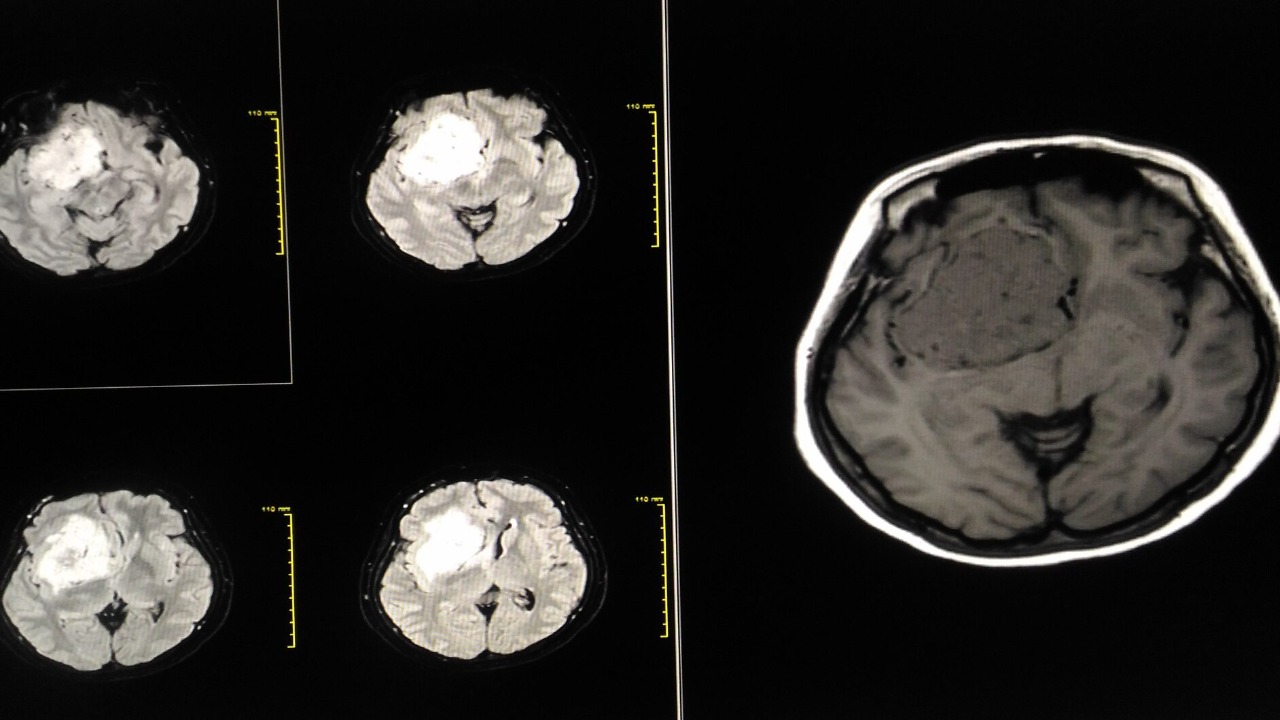

Amyloid-beta plaques are a hallmark of Alzheimer’s disease, accumulating in the brain and leading to neuronal toxicity and cognitive decline. Interestingly, these same plaques exhibit inhibitory effects on cancer pathways, such as apoptosis resistance in tumor cells. The study from the University of California, San Diego, highlights how amyloid-beta’s aggregation state influences its toxicity in neurons while offering potential as a targeted agent against aggressive cancers like glioblastoma. Lab experiments have shown that amyloid-beta selectively binds to cancer cell membranes, disrupting their growth [source].